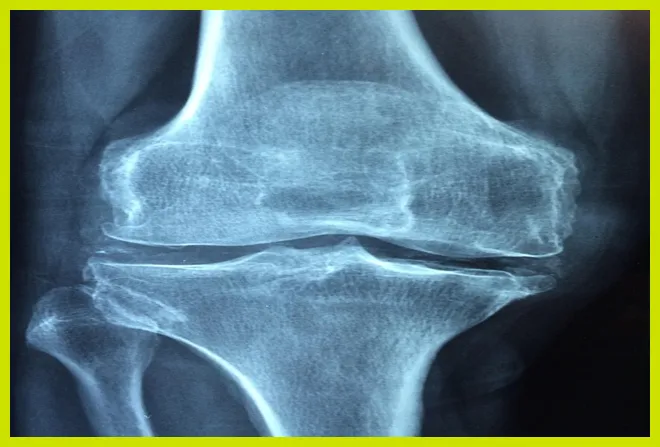

- 관절염: 퇴행성 관절염, 염증성 관절염 등으로 인해 고관절의 연골이 손상되면서 통증이 발생할 수 있습니다.